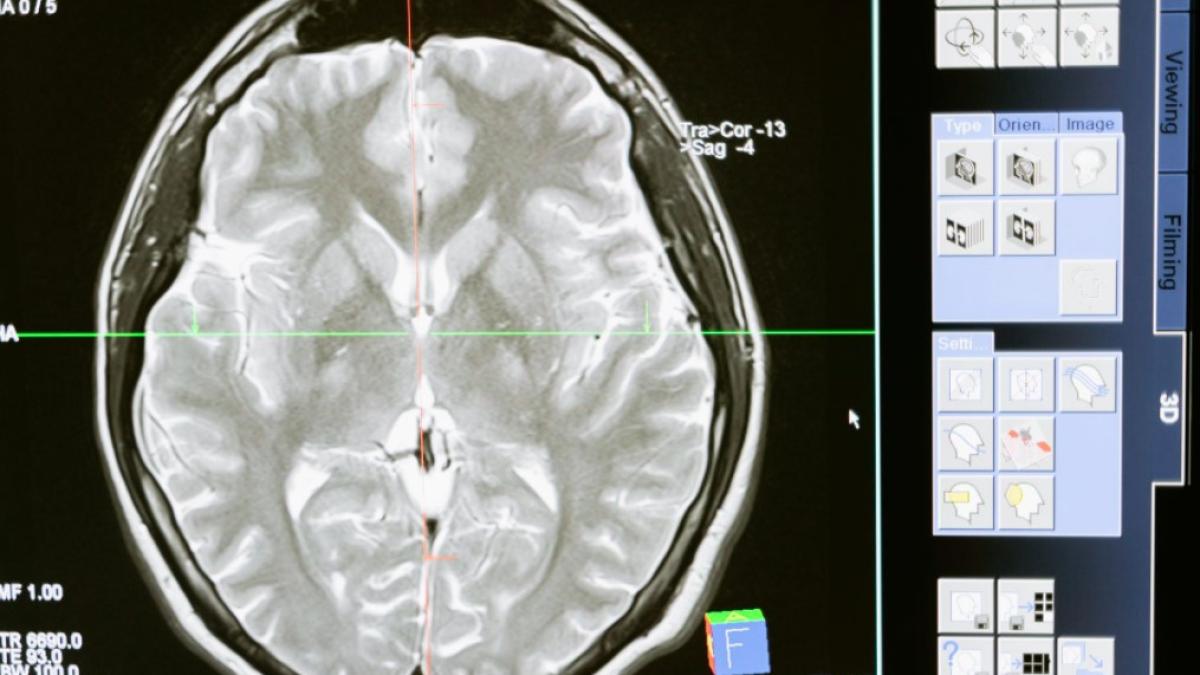

tumoare_cerebrala_ilustrativ_pexels_international_03669600 Foto: Pexels. Imagine cu rol ilustrativ

Două persoane cu un tip avansat de cancer cerebral au răspuns pozitiv la un tratament experimental dintr-o combinație de citostatice și medicamente imunoterapice, în Marea Britanie.